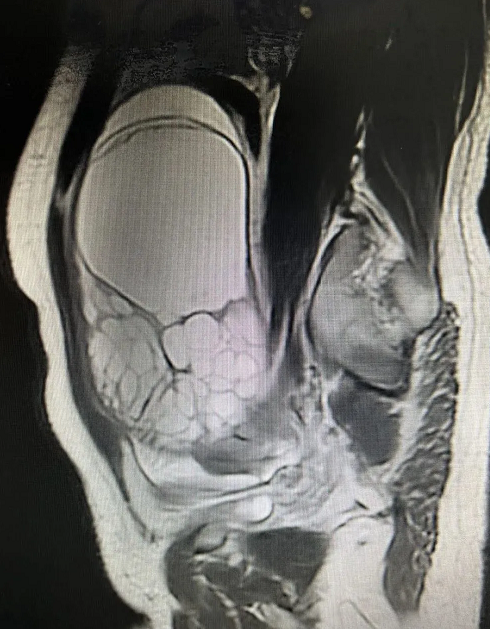

近日,海軍軍醫(yī)大學第二附屬醫(yī)院(以下簡稱“海軍醫(yī)二院”)婦產(chǎn)科主任劉曉軍教授團隊采用上海微創(chuàng)醫(yī)療機器人(集團)股份有限公司(02252.HK,以下簡稱“微創(chuàng)機器人”)研發(fā)的圖邁?單臂單孔腔鏡手術(shù)機器人,通過臍上切口,為兩名女性患者分別成功實施卵巢巨大腫瘤切除術(shù)和全子宮切除+雙側(cè)輸卵管切除術(shù),兩項手術(shù)取得圓滿成功。